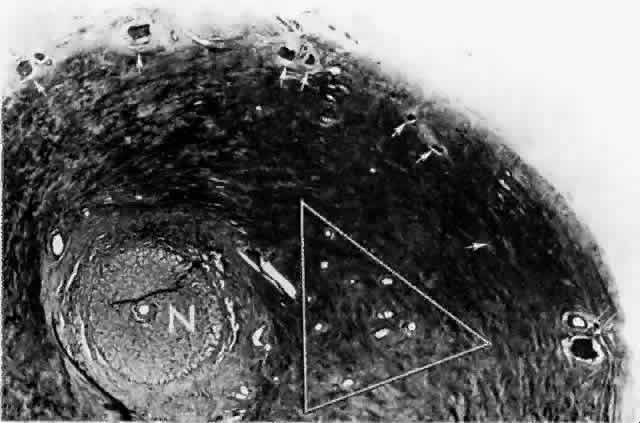

artery.  Fig. 15. Peripapillary sclera nasal to optic nerve (N). Cluster of short posterior ciliary arteries (SPCAs) (white triangle) is nasal to disc in this specimen. Other SPCAs form a ring around the

nerve. Short posterior ciliary nerves (arrows) form a wreath approximately 2 mm from the nerve. Emissary canal (thin, double arrow) for long posterior ciliary nerve (below) and artery. Cross-section at level of lamina cribrosa. (H & E, × 31) Fig. 15. Peripapillary sclera nasal to optic nerve (N). Cluster of short posterior ciliary arteries (SPCAs) (white triangle) is nasal to disc in this specimen. Other SPCAs form a ring around the

nerve. Short posterior ciliary nerves (arrows) form a wreath approximately 2 mm from the nerve. Emissary canal (thin, double arrow) for long posterior ciliary nerve (below) and artery. Cross-section at level of lamina cribrosa. (H & E, × 31)